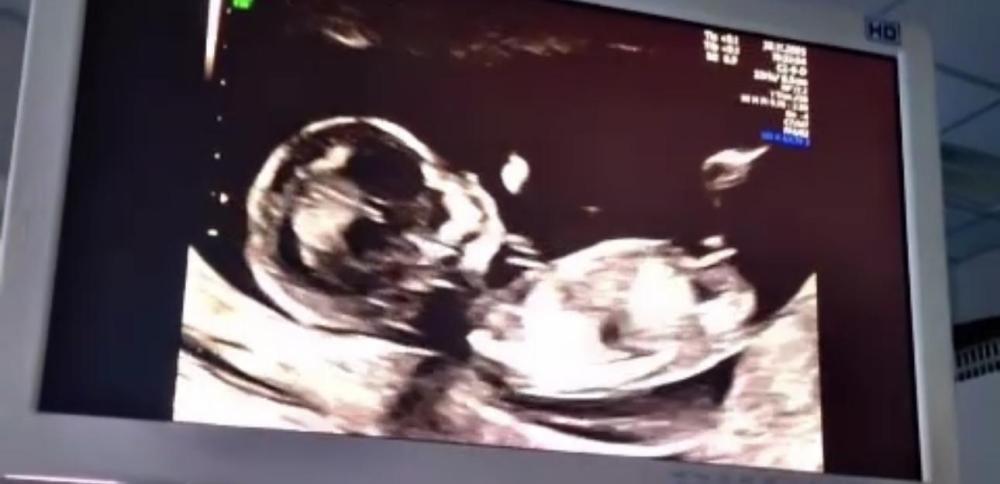

AnonymBruker Skrevet 2 timer siden #1 Skrevet 2 timer siden Hva synes dere om nub theory? Jeg har betalt for å gjette kjønn på nub theory metode og de sa 98% gutt. Viktigste er sikkert frisk baby men ønsker jente da jeg har 2 gutter fra før og vi tenker det siste barn 🥹Hva synes dere? Anonymkode: 94184...bc6

AnonymBruker Skrevet 2 timer siden #2 Skrevet 2 timer siden Hm noen bilder gutt noen jente. Best å vente ❤️ Anonymkode: 8656f...c6e

AnonymBruker Skrevet 2 timer siden #3 Skrevet 2 timer siden De mener de nederste bilde der kjønnet ses så ut som penis men er ikke det lårbein? Jeg må uansett vente er bare så spent. Anonymkode: 94184...bc6

AnonymBruker Skrevet 2 timer siden #4 Skrevet 2 timer siden AnonymBruker skrev (1 minutt siden): De mener de nederste bilde der kjønnet ses så ut som penis men er ikke det lårbein? Jeg må uansett vente er bare så spent. Anonymkode: 94184...bc6 Usikker. Om det er lårbeinet synes jeg det som ser ut som nub på de andre bildene er gutt. Anonymkode: 8656f...c6e

R2507 Skrevet 2 timer siden #5 Skrevet 2 timer siden AnonymBruker skrev (7 minutter siden): Hm noen bilder gutt noen jente. Best å vente ❤️ Anonymkode: 8656f...c6e De mener de nederste bilde der kjønnet ses så ut som penis men er ikke det lårbein? Jeg må uansett vente er bare så spent.